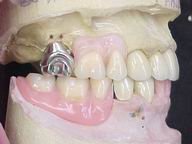

Reabilitação funcional e estética em ambas as arcadas

com próteses fixas e removíveis de encaixe de precisão.

Fase Intermediária Vista Frontal